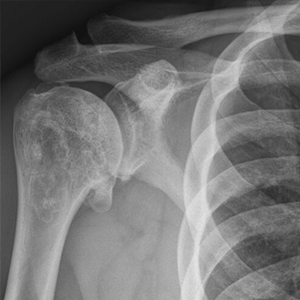

- This is a case example of a patient in his 40s who presented to us with severe shoulder pain, inability to work out and even raise his shoulder to chest level! At 6 months postoperatively he is back to the activities that he wants, keeping him active and healthy again